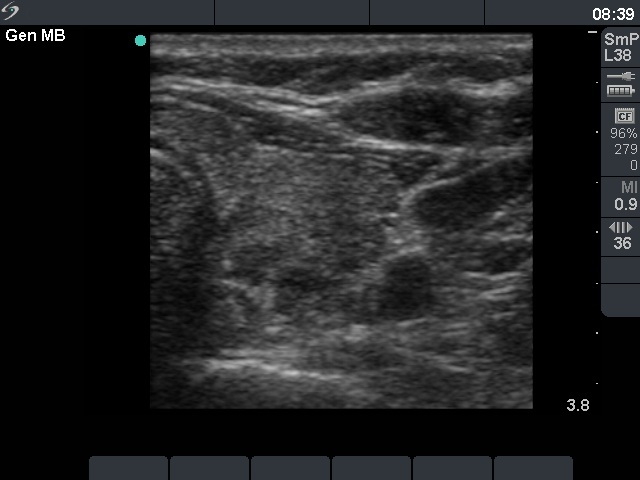

Ultrasonography: There was no parenchyma according to the right lobe, while there was a relatively large thyroid tissue in the left lobe. The latter displayed increased vascularization.